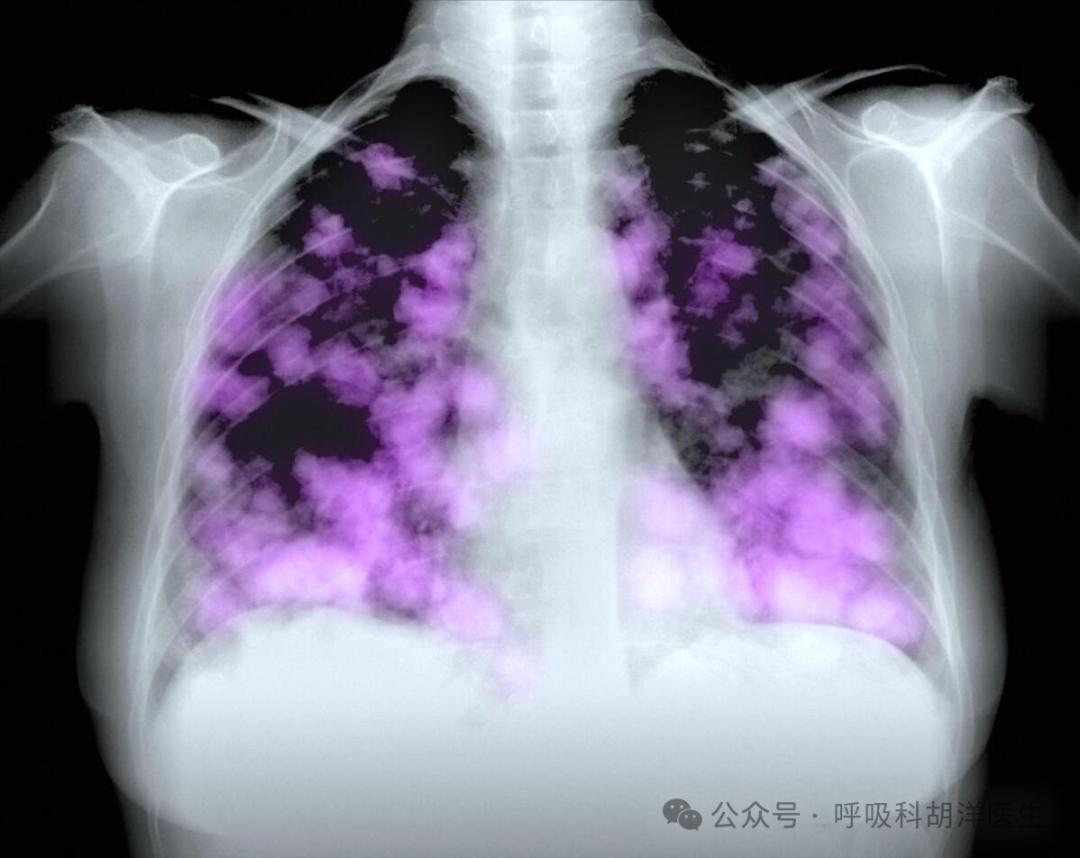

为什么肺癌会夺走人们的生命?看完这篇文章,你会重新认识肺癌。

首先,肺癌不是一种局部疾病,而是一种器质性疾病。虽然它生长在肺部,但它可以通过各种方式影响全身,如内分泌系统,这会导致人们缺乏力量、食欲不振和某些疾病。

肺癌可以产生无数种不同的疾病,同样是肺癌,有的人咳嗽发病,有的人气喘开始,有的人发现肺部没有疾病,相反,其他地方先发病, 例如有些人首先在脑海中发现肺癌转移瘤,手术后才发现肺癌转移。

4.肺癌很难用药物治愈。目前,所有临床药物都无法应对晚期肺癌。晚期肺癌最终会对各种药物产生耐药性,所以大多数肺癌的保守治疗只是为了限制。 延缓肿瘤的生长。